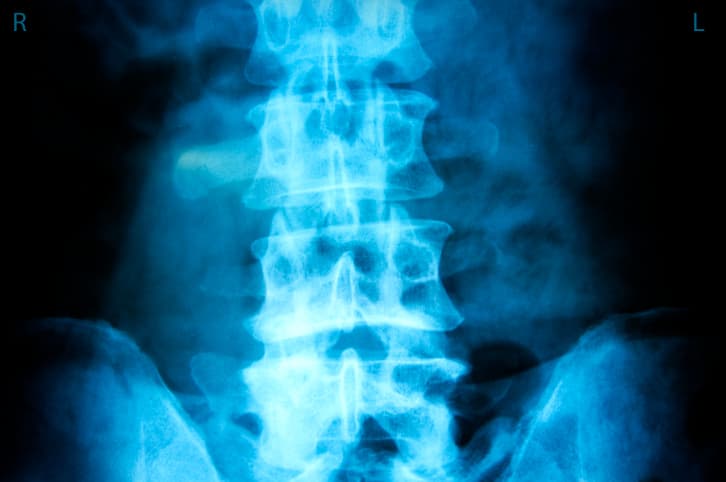

Dañan los discos lumbares

El movimiento de balanceo sobre la espalda que se realiza con el crunch clásico desgasta los discos vertebrales; especialmente la variante en la que se eleva el cuerpo y se da un giro hacia un lado para trabajar los oblicuos.

Una consecuencia a largo plazo del ejercicio en el suelo es una hernia discal, que ocurre cuando el centro de uno de los discos es empujado hacia afuera por el desgaste de los cartílagos.